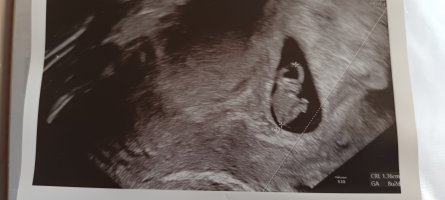

Er det noen som har vært på ultralyd rundt uke 7+6? Jeg har bestilt time til da og er så spent på hva vi får se! Gjerne sleng med bilde om dere har

Skikkelig fint bildeVis vedlegget 382557

Dette var vel 7+5, hode, rumpe, arm og fot ses her. Ikke mye en se så tidlig, men vi var for å se etter hjerteslag og det fikk vi se.